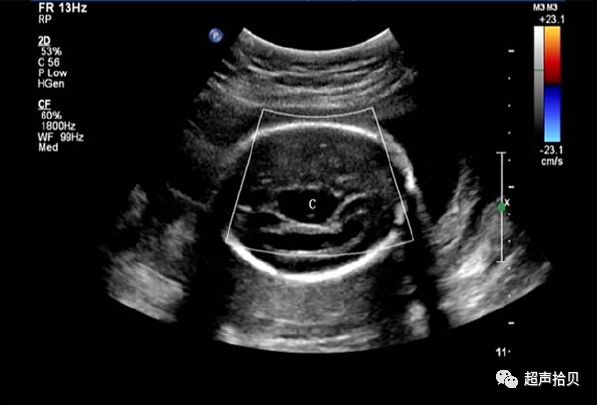

图1:横向声像图显示位于中线蛛网膜囊肿(C), 彩色多普勒没有血流显示;

1)脑内脑中线第三脑室后方或颅后窝内圆形、椭圆形或不规则形囊性暗区,壁薄光滑。

3)CDFI:囊内未见明显血流信号。